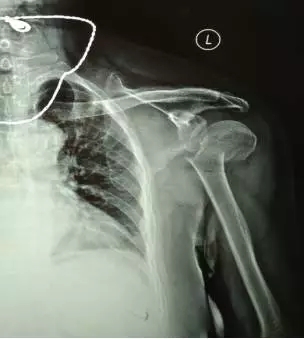

70多歲的鮑阿婆在家人陪同下來(lái)到上海大團(tuán)醫(yī)院就診。大團(tuán)醫(yī)院的醫(yī)生給鮑阿婆左肩部做了X線片檢查。片子拍出來(lái)竟然是左肱骨近端粉碎性骨折。外科頸,大結(jié)節(jié)都碎了,而且骨折端移位很嚴(yán)重。

正骨科的虞杰主任、邵鵬及葉華磊醫(yī)生看到鮑阿婆的片子也是一皺眉頭,這么厲害的骨折,還真是少見(jiàn),而且移位這么嚴(yán)重,手法復(fù)位的難度也是相當(dāng)大的。不過(guò)患者的信任給了他們很大的動(dòng)力,即使困難也要盡力幫患者。

整復(fù)前